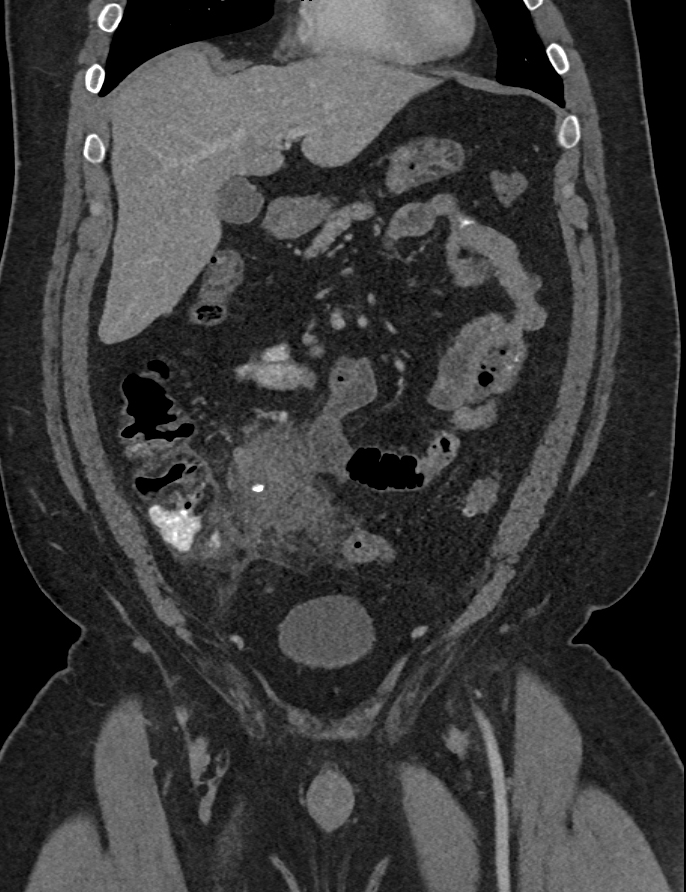

2) In this patient with RLQ pain the most likely diagnosis is?

Crohn’s disease

cecal cancer

small bowel lymphoma

appendicitis with periappendiceal abscess